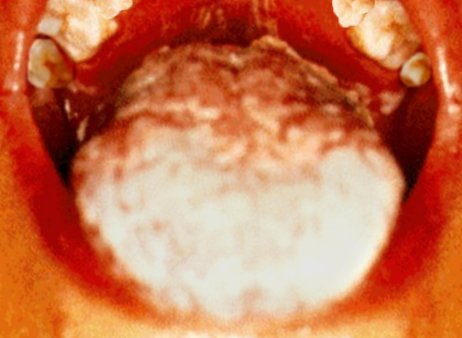

Oральный кандидоз

На небе пациента (вверху) и на языке (внизу) присутствуют симптомы орального кандидоза, оппуртинистическая грибковая инфекция